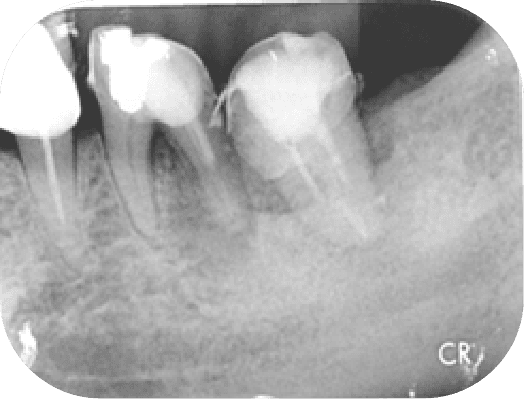

病人左下最後兩顆大臼齒在多年前有做過根管,重新治療時因為有顯微鏡輔助可以將之前清潔不下去的根管順利處理好。